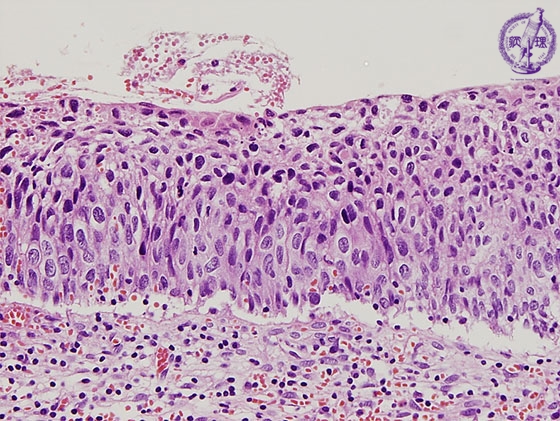

- ★(4)Cervical intraepithelial neoplasia

Histology (HE stain, high power): Carcinoma in situ (CIN or CIN3). Atypical cells with nuclear enlargement and markedly elevated nuclear density proliferated in full thickness of epithelium, but without concomitant invasion through the basement membrane (blue dotted line)